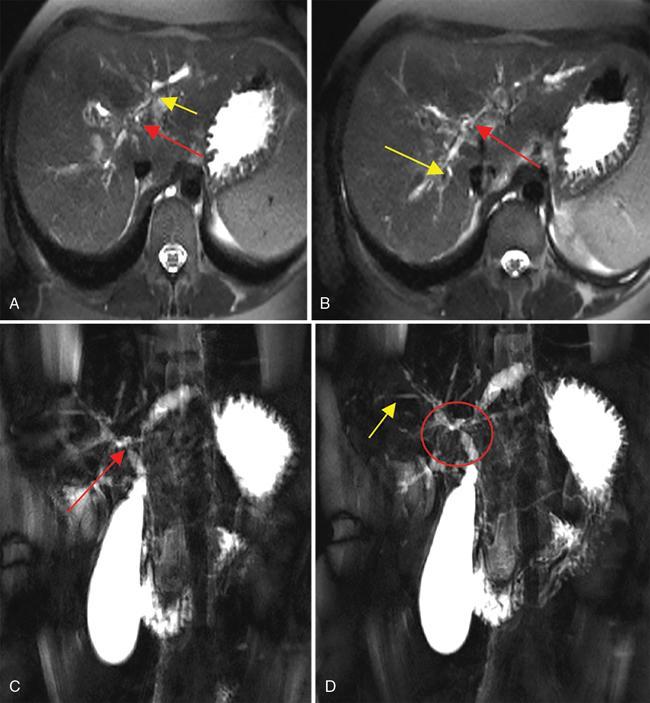

Ritu K. Kashikar, Shrinivas B. Desai, Chandresh Karnavat, Nilesh Doctor The biliary tract is subject to a variety of abnormalities. The spectrum includes benign diseases of autoimmune, infective, ischaemic, infiltrative aetiologies and malignant disorder, which most importantly represents cholangiocarcinoma. Imaging in particular magnetic resonance cholangiopancreatography (MRCP) plays a vital role in diagnosis and follow-up of these disorders. Multidetector computed tomography (MDCT) and magnetic resonance imaging (MRI) are also crucial in preoperative staging of biliary malignancies and making decisions regarding resectability and extent of resection. This chapter focuses on important benign and malignant disorders of the biliary tree and imaging features that aid in differentiation of various entities. A variety of disorders affect the biliary tree. Most biliary disorders manifest as biliary dilatation. The various causes are listed in Table 9.15.1. Imaging plays an important role in identification of aetiology based on pattern of involvement in association with clinical picture. USG is often the first investigation in a patient with jaundice. USG is excellent at showing biliary dilatation. It may be useless in assessing level of obstruction and biliary stones. Changes in liver morphology, development of cirrhosis is accurately done on USG. Early changes in conditions like primary sclerosing cholangitis (PSC), presence of intrahepatic ductal strictures, thickening of common bile duct (CBD) are, however, not confidently seen and need imaging modalities like MRCP and computed tomography (CT). Staging of hilar cancers is also best done on CT or MRI with contrast. Contrast-enhanced CT is extremely accurate in staging hilar cancers. It is a preferred modality to access radial spread of the disease and vascular involvement. Subtle changes of PSC and autoimmune cholangitis may however be missed and MRCP is preferred in these conditions. The protocol for evaluating biliary disease is standard plain scan followed by early, late arterial, portal venous and parenchymal phases similar to that obtained for focal liver lesions. Delayed phase images should be obtained for hilar malignancies, which often show delayed enhancement. MRCP with or without contrast is the modality of choice in diagnosing and characterizing biliary diseases. Owing to its noninvasive nature, it has replaced endoscopic retrograde cholangiopancreatography (ERCP) in the initial evaluation and follow-up of a variety of biliary pathologies. Absence of radiation exposure makes it suitable to obtain follow-ups in patients requiring serial scanning. The ability to diagnose abnormalities of both intra- and extrahepatic biliary tree, level of obstruction, longitudinal and radial spread of neoplastic process make it an ideal modality. MRCP protocol includes T2 weighted single-shot fast spin-echo, T1 weighted in phase and opposed phase gradient echo, diffusion-weighted imaging, T2-weighted fat-suppressed fast spin-echo in axial and coronal. A pre contrast three-dimensional T1-weighted fat-suppressed spoiled gradient-echo image is obtained in addition to 3-D MRCP. Postcontrast protocol includes dynamic three-dimensional T1-weighted fat-suppressed spoiled gradient-echo (in arterial, late arterial and portal venous, parenchymal and delayed phases). Since the advent and widespread use of MRCP, the utility of ERCP in diagnosing biliary pathologies has significantly reduced. ERCP is primarily used when stenting or other procedures need to be performed in the same setting. Although an invasive procedure with postprocedural risk of pancreatitis ERCP allows excellent depiction of biliary changes in conditions like PSC, recurrent pyogenic cholangitis (RPC) and IgG4-related disorders. Endoscopic USG (EUS) is an excellent modality in diagnosing lower bile duct pathologies and also has the added advantage of obtaining a biopsy in the same setting. EUS is less invasive than ERCP and overall safer. PSC is a premalignant cholestatic liver disorder characterized by bile duct strictures secondary to bile duct inflammation and fibrosis. Cirrhosis of liver can develop secondary to this condition and patients are at a high risk for biliary and colonic cancers. PSC is a relatively rare disease, with an incidence of less than 50 per 100,000 patients though it varies in various location. It is diagnosed in young patients aged 30–40 years and is twice as common in men than in women. Similar to other autoimmune diseases, genetic susceptibility is likely to be instrumental in the development of PSC after exposure to a trigger. There is also a strong association between PSC and human leukocyte antigens (HLAs). Environmental factors such as childhood microbial exposure also play an important role in disease pathogenesis. A strong association of PSC with inflammatory bowel disease (IBD) is seen. There is a 100-fold increased risk of developing PSC among siblings. PSC can be asymptomatic but may present with cholestatic symptoms such as jaundice, pruritus, fatigue and right upper quadrant pain, steatorrhoea and episodes of acute bacterial cholangitis. There is marked elevation of alkaline phosphatase (ALP). A twofold to threefold increase in serum alanine and aspartate aminotransferase (AST) can be seen. Elevated bilirubin is usually seen in advanced disease, malignancy or those with choledocholithiasis. Various serum antibodies can also be elevated in PSC. These have been enlisted in Table 9.15.2. On liver biopsy, classic pathologic features of periductal concentric fibrosis or ‘onion skin’, around the affected ducts can be seen. This is however not a pathognomonic finding and is seen in less than 40% of biopsy specimens. Therefore, biopsy is not routinely used as a diagnostic tool for PSC and is reserved primarily for disease staging. MRI with MRCP best depicts the biliary changes in PSC and is the modality of choice. While CT and USG may show biliary dilatation and changes of cirrhosis in advanced cases, they fail to show early changes (Table 9.15.3). USG is an effective modality for the visualization of dilatation and diffuse wall thickening of the extrahepatic bile duct. Other feature seen on USG is bright echogenic portal triad. However, the role of USG in the diagnosis of early PSC is limited owing to suboptimal assessment of the intrahepatic biliary ducts. Features of advanced disease such as heterogeneous coarse echogenicity can be readily detected with USG. The major benefit of performing US is to guide liver biopsy. Also, liver stiffness as assessed by transient elastography correlated well with the degree of liver fibrosis in PSC patients. CT can demonstrate some findings suggestive of sclerosing cholangitis such as focal, discontinuous, often peripheral intrahepatic biliary duct dilatation and thickening with enhancement of the bile ducts owing to inflammation. CT is effective in helping exclude other causes that can result in biliary stasis and dilatation such as hepatic and pancreatic lesions. CT is also excellent in diagnosing tumours, which may sometimes have similar presentation. Concomitant changes of IBD, if present, can be seen. However, CT is limited in assessment of biliary strictures and visualization of disease involving small peripheral bile duct, especially in the early stages of the disease. CT shows changes of cirrhosis in liver and assessing changes of portal hypertension. MRCP is diagnostic imaging modality of choice in the workup of patients with suspected PSC, as recommended by both the AASLD and EASL guidelines. MRCP has high diagnostic sensitivity (86%) and specificity (94%) for the detection of PSC (Table 9.15.3). Multifocal short segmental strictures in the intra- or extrahepatic biliary tree with intervening normal or dilated duct leading to beaded appearance are seen in early disease. The location in strictures is usually at the biliary bifurcation and are disproportionate to upstream dilatation. Advanced cases show pruning of peripheral biliary radicals secondary to advancing fibrosis obliterating the smaller ducts. An obtuse angle between the central and peripheral ducts is suggestive of PSC. Diverticula and webs also can be seen, though not pathognomonic (Table 9.15.4) (Figs. 9.15.1–9.15.3). Strictures of the CBD of less than 1.5 mm and of left, right or common hepatic duct (CHD) of less than 1 mm are defined as dominant stricture. A dominant stricture is associated with worse prognosis in part due to development of cholangiocarcinoma. MRCP plays an important role in raising the suspicion and guiding treatment. A dominant stricture may be confused with hilar cholangiocarcinoma on imaging and it is often impossible to distinguish the two based on imaging alone (Table 9.15.4) (Fig. 9.15.4). Changes in liver morphology are seen in the form of distortion. The classical change described in PSC includes hypertrophy of the caudate lobe and atrophy of the left lateral and right posterior segments of the liver. Hypertrophy of caudate lobe is more frequent in PSC than cirrhosis from other aetiologies. Other parenchymal changes include heterogeneity of liver, periportal cuffing, peripheral inflammation, cirrhosis and features of portal hypertension. Hyperintensity of the liver parenchyma in PSC on nonenhanced T1-weighted images has been reported. Wedge-shaped peripheral atrophic areas of confluent hepatic fibrosis are seen as high T2-weighted signal intensity. Periportal oedema is visualized as high signal intensity in periportal region on T2-weighted. Increased heterogeneous peripheral enhancement of the liver parenchyma can be seen and is likely due to the altered blood supply in those areas in response to parenchymal inflammation (Table 9.15.4) (Figs. 9.15.5 and 9.15.6). MR elastography is the most accurate noninvasive method for the diagnosis and staging of liver fibrosis and could potentially replace liver biopsy. It is predictive of progression to decompensated liver disease. However, lack of wide availability are still major limiting factors. MR elastography is not influenced by obesity or anatomical conditions (e.g. narrow intercostal spaces and ascites) and the sample size of the liver is significantly higher and hence has several advantages over ultrasound elastography (Table 9.15.5). Besides these features, enlarged reactive abdominal lymph nodes, commonly periportal and portocaval lymph nodes, are commonly diagnosed in PSC and should not be misdiagnosed as a lymphoproliferative disorder or metastatic disease. Though ERCP has higher diagnostic accuracy in detecting PSC, its role is limited to intervention required in PSC due to its invasive nature and potential complications. Also it is recommended that MRCP be performed prior to ERCP as a preprocedural MRCP can provide a road map to the endoscopist. Small duct PSC is a variant PSC syndrome with biochemical markers and histologic features suggestive of PSC with normal cholangiography. It is associated with better prognosis. Approximately one-fourth of patients’ progress to classic PSC in an average of 8 years. Bile duct calculi are a common complication of PSC. Pigmented bile duct stones are common owing to biliary stasis. Both intrahepatic and extrahepatic biliary stones can be found. However, the presence of biliary tree stones is not an essential diagnostic feature. Soft calcific foci within dilated bile ducts can be seen on US and CT images. MRI with MRCP is the imaging modality of choice to detect bile duct stones and appear as focal areas of signal-intensity-void filling defects on T2-weighted images. Usually isointense at T1-weighted imaging but frequently are hyperintense. The presence of biliary strictures puts these patients at risk of bacterial cholangitis in PSC patients. The classic Charcot triad of fever, abdominal pain and jaundice can be seen. Early enhancement of the biliary wall due to the biliary duct inflammation is a common finding with peribiliary reactive hepatic parenchymal changes. Cholangitic abscesses may sometimes be seen. PSC patients are at high risk of developing cholangiocarcinoma during the disease course with and a total risk of 10%–15%. Approximately 30% of all cholangiocarcinomas are detected within the first year of establishing a diagnosis of PSC and so it is important to be suspicious even at the time of PSC diagnosis and to survey for early detection. Rapid clinical deterioration, worsening of jaundice, pruritus, weight loss along with elevation in serum bilirubin and ALP should raise suspicion of PSC. It may be difficult to distinguish benign from malignant strictures. Progressive bile duct wall thickening, irregularity, enhancement, new onset biliary dilatation, dominant stricture or development of focal strictures with dilatation and ipsilateral atrophy are indeterminate features that may raise possibility if occult cholangiocarcinomas. Perivascular thickening, vascular involvement or occlusion are features favouring malignancy. Definite diagnosis is however often not possible on imaging alone and a brush biopsy should be taken in patients with new onset clinical symptoms, elevated tumour makers or above-mentioned indeterminate imaging features (Table 9.15.7). The most common subtype of cholangiocarcinoma in PSC patients is periductal type, characterized by long segment irregular wall thickening along the bile duct with no identifiable mass. The lesion is hypointense on T1W1 images and hyperintense on T2W1 images showing progressive enhancement on contrast study. The tumour could be at the bifurcation and can cause abrupt cut-off, commonly presenting as Klatskin tumour (Fig. 9.15.7). Combined UC and PSC is associated with a higher risk for colorectal carcinoma than UC alone. PSC is considered as an independent risk factor for development of colorectal carcinoma in patients with UC. Malignancy tends to involve the right colon or more proximal parts of the colon. Clinical presentation and history in patients with ascending cholangitis differ from those with PSC. Fever, pain and jaundice dominate the presentation in patients with ascending cholangitis while patients with PSC may be asymptomatic. The typical findings of PSC including biliary duct stenosis, beading or pruning are not typical findings in the newly diagnosed cases of acute ascending cholangitis. Wedge-shaped peripheral and/or intrahepatic peribiliary foci of increased T2 signal around the dilated radicals with arterial and/or delayed parenchymal enhancement has been described in ascending cholangitis. Patients with RPC present with recurrent episodes of abdominal pain, fever, jaundice and chills. These features differ from those in patients with PSC. Hepatolithiasis with pigmented stones in the biliary tree and upstream and downstream duct dilatation are typical imaging features in RPC (Table 9.15.8). Ischaemic cholangiopathy is a form of biliary injury resulting from decreased arterial supply. History of liver transplantation is the key in diagnosing ischaemic cholangiopathy. Biliary strictures in AIDS cholangiopathy are indistinguishable from PSC. However, the combination of papillary stenosis and intrahepatic ductal strictures appears relatively unique to AIDS cholangiopathy; this combination is not found in PSC. Clinical history may help to distinguish one from the other. Effective medical therapy for PSC is lacking. Oral ursodiol (ursodeoxycholic acid) is one of the main treatment options of cholestatic diseases though does not prevent disease progression. Azathioprine and steroids are recommended for use in patients with AIH as well as those with AIH–PSC overlap syndrome. Vedolizumab is a gut-specific monoclonal antibody that has been tried but the clinical utility in PSC–IBD patients remains under investigation. Dilatation of biliary strictures, stenting, lithotripsy and stone extraction can be done with the aid of ERCP and percutaneous transhepatic cholangiography (PTC). The only definitive cure of PSC is, however, liver transplantation. Treatment of complications like choledocholithiasis stone removal can be accomplished by using standard endoscopic techniques with or without sphincterotomy, with balloon or basket extraction for extrahepatic biliary stones. For bacterial cholangitis, immediate administration of broad-spectrum antibiotic therapy is recommended and in abscess formation percutaneous drainage with intravenous antibiotic therapy shows favourable outcome compared with surgical drainage. Incidence is 20%–25%. Diagnosis of recurrent PSC requires careful evaluation, as there are other causes of biliary changes after liver transplant with similar features. Nonanastomotic biliary strictures imply the diagnosis of recurrent PSC only if they occur more than 90 days after transplant. Characteristic multifocal strictures and segmental dilatations of biliary ducts are suggestive findings. MRCP is the initial modality. RPC is characterized by a triad of recurrent biliary sepsis, inflammatory biliary strictures and intrahepatic stones. Fifty per cent of patients may have acute pancreatitis. Oriental cholangiohepatitis, primary hepatolithiasis, Hong Kong disease and oriental infestational cholangitis. Prevalence in the third and fourth decades of life with equal frequency among men and women peak. Southeast Asia predominantly in rural population and in lower socioeconomic groups. Gut-derived organisms lead to sepsis, which initiates a cascade of events, which leads to a chronic, progressive and recurrent inflammatory process in cholangioles. Associations with Clonorchis sinensis, Opisthorchis species, Fasciola hepatica and Ascaris lumbricoides infestations have been suggested. Common organisms cultured from bile include Escherichia coli, Klebsiella, Pseudomonas and Proteus species and anaerobes. Structural biliary abnormalities may develop before stones are demonstrable. Strictures may be seen at cholangiography without stones and vice versa. Entrapped stones cause stasis, sepsis, scarring and stricturing with the increasing lithogenicity (Table 9.15.9). Typically present with abdominal pain, fever and jaundice (the Charcot triad) and commonly provide history of repeated episodes. Routine investigations may demonstrate leukocytosis, deranged liver enzymes with obstructive pattern. Elevated cholestatic markers (bilirubin, ALP and gamma GT) and deranged LFTs can be seen. Serum inflammatory markers can be elevated. Additional tests aiding in differential diagnosis include autoantibodies, ANCA, CA19-9 and serologic tests for Echinococcus. Histology is usually not required. It shows fibrous mural thickening of bile ducts and periductal tissue, as well as acute and chronic inflammatory changes. The imaging features include changes in bile ducts, development of calculi and changes in the parenchyma. The disease affects intrahepatic ducts more than the CHD and CBD. Disproportional dilatation of central intrahepatic ducts and extrahepatic bile ducts is seen with nondilated or minimally dilated peripheral ducts, leading to abrupt tapering of bile ducts. All segments of biliary tree may be involved, but the lateral segment of the left lobe is most often and extensively involved most likely because left hepatic ducts come off at a more acute angle compared with the right hepatic ducts, thus predisposing to stasis and stricture formation (Table 9.15.10). Hepatolithiasis is common in patients with RPC. Stones are composed mainly of bile pigments with variable calcification. There may be single or multiple stones scattered in the intra- or extrahepatic ducts or both. The dilatation of the extrahepatic duct is generally not related to the location of the stone. Ducts both proximal and distal to the stone are dilated. Parenchymal atrophy most commonly involves the left lateral and right posterior segments while hypertrophy of the caudate and right lobe is seen. USG shows dilatation of the central intrahepatic and extrahepatic ducts, with relative sparing of the peripheral biliary tree. Hepatolithiasis can be seen in 90% of cases. The echogenicity and acoustic shadowing of calculi may vary depending on extent of calcification. There is often associated periportal echogenicity. Ultrasound may be useful in performing image-guided percutaneous drainage of abscesses or biopsy of suspicious lesions. Limitations include inability to detect subtle intrahepatic ductal dilatation and heavy stone burden obscuring evaluation of underlying hepatic parenchyma. Contrast-enhanced CT is increasingly being used as first line of imaging. It allows for detection of characteristic disproportionate dilatation of the extrahepatic and central intrahepatic ducts. Contrast-enhanced CT also allows for detection of bile duct wall enhancement, suggestive of acute cholangitis. Ninety per cent stones are hyperdense to liver parenchyma on nonenhanced scan. Extent of calcification in calculi may vary. Parenchymal atrophy affects left lateral segment most frequently, followed by right posterior segments. Eventually, changes of cirrhosis can be seen. Heterogeneous appearance of liver parenchyma with segmental steatosis and altered enhancement can be seen particularly during acute attack. Pneumobilia is not infrequent and can usually be attributed to recent procedures or surgeries like bilioenteric anastomosis. It may, however, be seen in patients without history of prior interventions due to recent passage of stone through the ampulla or less commonly cholangitis related to gas forming organisms (Fig. 9.15.8). Subtle intrahepatic ductal strictures and noncalcified stones may be missed on CT. MRCP allows visualization of both intra- and extraductal disease and can reveal complete extent, severity and complications of the disease. Even noncalcified calculi which may be missed on CT or sonography, are seen as intraductal filling defects on heavily T2-weighted images and may appear hyperintense to the liver on T1-weighted images. MRI demonstrates central and extrahepatic duct dilatation with decreased arborization and abrupt tapering of peripheral ducts. MRI particularly MRCP sequences accurately depicts stenotic segments and delineates the entire biliary tree, including the proximal part of the stricture, without risk of aggravating biliary sepsis. Even short segment duct strictures <1 cm are easily seen on MRCP (Figs. 9.15.8 and 9.15.9). Parenchymal abnormalities like hepatic atrophy, whether diffuse or segmental, and altered signal can be accurately diagnosed. Mass lesions and hepatic abscesses, if present, are also well delineated. The characteristic finding of disproportionate dilatation of the ducts, with multiple intraductal calculi are well demonstrated. There may also be intrahepatic strictures, with abrupt tapering of the peripheral ducts as well as decreased arborization of the biliary tree (arrowhead appearance). It allows for better spatial resolution, thus permitting better evaluation of the smaller peripheral ducts. The main limitation of ERCP is its invasive nature, with complications such as ERCP-associated pancreatitis. Heterogeneous parenchymal enhancement, wall thickening and periductal enhancement are seen in acute cholangitis. Abscess formation is encountered in up to 20% of RPC patients who undergo cross-sectional imaging. The abscesses can occur in both the affected and unaffected portions of the liver but most commonly seen in the right lobe. Sonography guided aspiration can be done when diagnosis is doubtful. Intrahepatic bile lakes are not infrequent and may or may not communicate with the biliary tree. On USG bilomas appear anechoic and are usually hypodense on CT with or without calculi. Leakage of bile from a severely dilated obstructed duct may lead to formation of extrahepatic biloma. Cholangiocarcinoma is the most feared complication and may be seen in up to 5% of patients. Segments with high stone burden or those with atrophy are more prone to developing cholangiocarcinoma. Clinical and laboratory indicators for development of cholangiocarcinoma in patients with PSC include increase in jaundice without associated cholangitis, sudden weight loss, significant elevation of ALP and rising tumour markers. Peripheral cholangiocarcinoma manifests as expansion of the affected segment. Hypoattenuating mass with showing peripheral enhancement causing narrowing of the portal vein may raise suspicion of malignancy. Portal vein thrombosis has also been reported but is rare. Recurrent biliary sepsis may lead to periductal inflammation and portal thrombophlebitis. Portal thrombosis can lead to lobar atrophy with compensatory hypertrophy of the uninvolved lobe. Higher incidence of hepatocellular carcinoma (HCC) is reported in patients with RPC due to development of cirrhosis in severe cases. Management should comprise antibiotic treatment, clearance of stones, maintenance of biliary drainage and long-term follow-ups. ERCP allows for therapeutic procedures such as stone removal and stenting of strictures. Destroyed liver segments, those with multiple abscesses and patients with secondary cholangiocarcinoma are candidates or surgery. Stone extraction can also be done surgically with the aid of basket, forceps, balloon catheter or flexible choledochoscope. Transduodenal sphincteroplasty and hepaticojejunostomy are commonly performed drainage procedures. Indications for transplantation include extensive bilobar hepatolithiasis, cirrhosis and liver failure. IgG4 cholangiopathy is a cholangitis characterized by elevated serum IgG4 and infiltration of the bile duct wall with IgG4 positive plasma cells leading to storiform fibrosis and obliterative phlebitis with resultant bile duct wall thickening. This condition shows good response to steroids. Frequent association with IgG4-related autoimmune pancreatitis is seen. IgG4 sclerosing cholangitis (IgG4-SC) has a threefold to fivefold higher prevalence in men than women. It usually presents in the fifth and sixth decades of life. Incidence of this disease is approximated to be around 0.28–1.08/100,000. Autoimmunity has been considered as the most probable pathogenesis of IgG4-related disease (IgG4-RD). Several HLA association have identified as determinants of disease susceptibility. The major histologic features associated with IgG4-RD have been well described and include the steps. Chronic or recurrent cholangitis is the most common presentation and seen in up to 75% cases. Other symptoms seen are fever, pruritus, pain and weight loss. Biliary involvement may be detected incidentally in patients being scanned for symptoms related to involvement of other organs such as pancreas. One-quarter of patients with IgG4-SC may be asymptomatic. Serum liver tests show a cholestatic pattern with often marked elevation of ALP and γ-GT and only mildly increased ALT and AST. Serum bilirubin may be increased. Tumour marker CA 19-9 is not able to distinguish pancreatobiliary malignancies from IgG4-SC since levels of >1000 IU/mL (ULN = 37 IU/mL) may be observed in IgG4-SC. IgG4 levels are elevated (>140 mg/dL) in up to 75%–80% of affected patients. A cut-off level of 207 mg/dL might be useful for completely distinguishing IgG4-SC from cholangiocarcinoma. Elevated bile fluid IgG4 has a high sensitivity and specificity of 100% at a cut-off level of 113 mg/dL and seen only in cases of IgG4-RD, neither PSC nor cholangiocarcinoma. Approximately 40% of patients have peripheral blood eosinophilia, often accompanied by asthma and atopy. Patients may show hypergammaglobulinemia, elevated serum IgE. Several diagnostic criteria have been developed to aid in the diagnosis of IgG4-SC. The most widely used is the HISORt (Histology, Imaging, Serology, other Organ involvement and Response to therapy) criteria of the Mayo Clinic. This tool was initially used to diagnose AIP but can be adapted to diagnose IgG4-SC by Ghazele et al. (Tables 9.15.13 and 9.15.14). It is often the initial investigation and may be normal early in the course of the disease. Circumferential thickening of the bile ducts with biliary dilatation is seen later in the disease. US also helps in the identification of associated findings affecting other organs. However, US has low sensitivity in detecting the disease and is suboptimal for assessing the extent of the disease. Contrast-enhanced CT though not the investigation of choice shows bile duct wall thickening with proximal mild dilatation. The intrapancreatic bile duct segment is more commonly involved. The most important finding is circumferential symmetric wall thickening of the bile ducts, frequently involving the extrahepatic segments, with smooth outer and inner margins. In addition, the thickened segment shows progressive homogeneous contrast enhancement, further increasing in the delayed phase. As opposed to malignancies, wall thickening or stricturing of bile ducts in IgG4-RD is not associated with proportionate proximal biliary dilatation (Figs. 9.15.10 and 9.15.11). In addition to the above findings, imaging findings of IgG4 disease affecting other organs, that is, gallbladder wall thickening, changes of autoimmune pancreatitis, retroperitoneal fibrosis and kidney findings can be seen. MRI is the investigation of choice. MRI findings are similar to CT findings and include circular and symmetric long segmental thickening of the bile duct wall with smooth outer and inner margins. Bile duct wall thickening can be seen in nonstenotic areas as well The other findings are the visibility of patent bile duct in the strictures, disproportionate proximal dilatation, hyperenhancement during the late arterial phase, homogeneous hyperenhancement during the delayed phase, concurrent gallbladder wall thickening and no vascular invasion (Table 9.15.15).